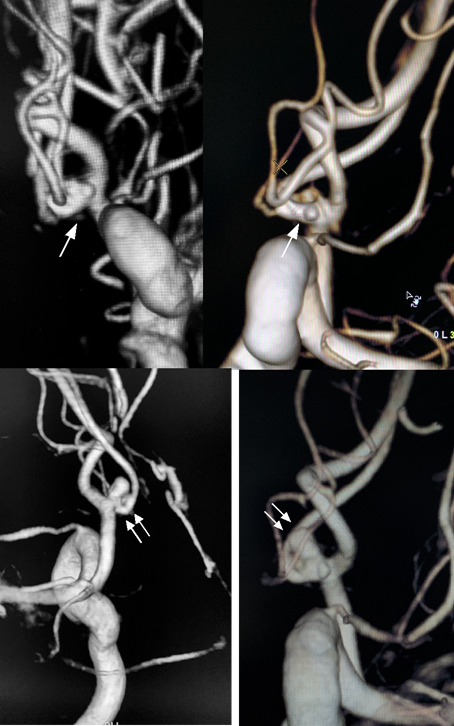

A 35-year-old previously healthy woman presented in emergency department complaining of severe headache, with a Grade 2 Hunt and Hess score. Neurological status was unremarkable. A computed tomography (CT) scan showed SAH (Modified Fisher Scale grade I) and the cerebrospinal fluid (CSF) sample showed 12.000 RBC/CC. Nevertheless, CT angiography did not depict any saccular aneurysm. Due to high suspicion, a three-dimensional rotational angiography was performed on day two, but showed only some minor AComA wall irregularities close to the left A1/A2 junction (Figure 1A). A second angiogram was performed 6 days later in order to elucidate the cause of the SAH and revealed a small pseudoaneurysm at this site (Figure 1B). Considering the acute morphological changes and the previous blending, we indicated urgent treatment. Microsurgical clipping occlusion of the AComA was discarded as an option since the lesion stretched out to the left A1/A2 segment. Since right A2 segment was supplied by right A1 segment, we decided to occlude AComA and the pseudoaneurysm with coiling and perform endovascular reconstruction of the left A1/A2 segments with a Flow Diverter Stent (FDS). The procedure was performed under general anesthesia and systemic heparinization (8000 IU during the procedure). The AComA occlusion was achieved with remodeling technique. A Scepter XC balloon 4 x 11m (Microvention Endovascular Inc., CA, USA) protected the left A1/A2 junction and three Microplex coils (Microvention Endovascular Inc., CA, USA) were detached through a Headway 17 microcatheter (Microvention Endovascular Inc., CA, USA). Finally, 2,5 x 14 x 20 mm Fred Jr Embolization Device (Microvention Endovascular Inc., CA, USA) (Figure 2) was placed through a Headway 21 microcatheter (Microvention Endovascular Inc., CA, USA), covering all the A1/A2 junction. Immediately after its placement, we administered intravenous abciximab 0.25 mg/kg bolus and maintenance dose for 12 hours. Dual antiplatelet therapy was initiated in the following day with clopidogrel 75 mg and aspirin 100 mg and kept for three months while aspirin was sustained for one year. External ventricular derivation was not required since there was no ventriculomegaly. Patient presented no evidence of new neurological deficits or complications such as rebleeding, regrowth, vasospasm, stent occlusion/stenosis or stroke. Control angiogram performed three months later confirmed exclusion of both pseudoaneurysm and the AComA (Figures 3) without any persistent arterial wall irregularity. Patient remained clinically stable with mRs 0.

Figure 1 On day one of hospitalization 3D angiography showed some minor irregularity of the AComA close to the left A1/A2 junction (arrow) (A and B). At day 7, 3D angiography revealed an pseudoaneurysm on the AComA (double arrow) with arterial wall irregularities on the AComA and on the left A1/A2 junction (C and D)..